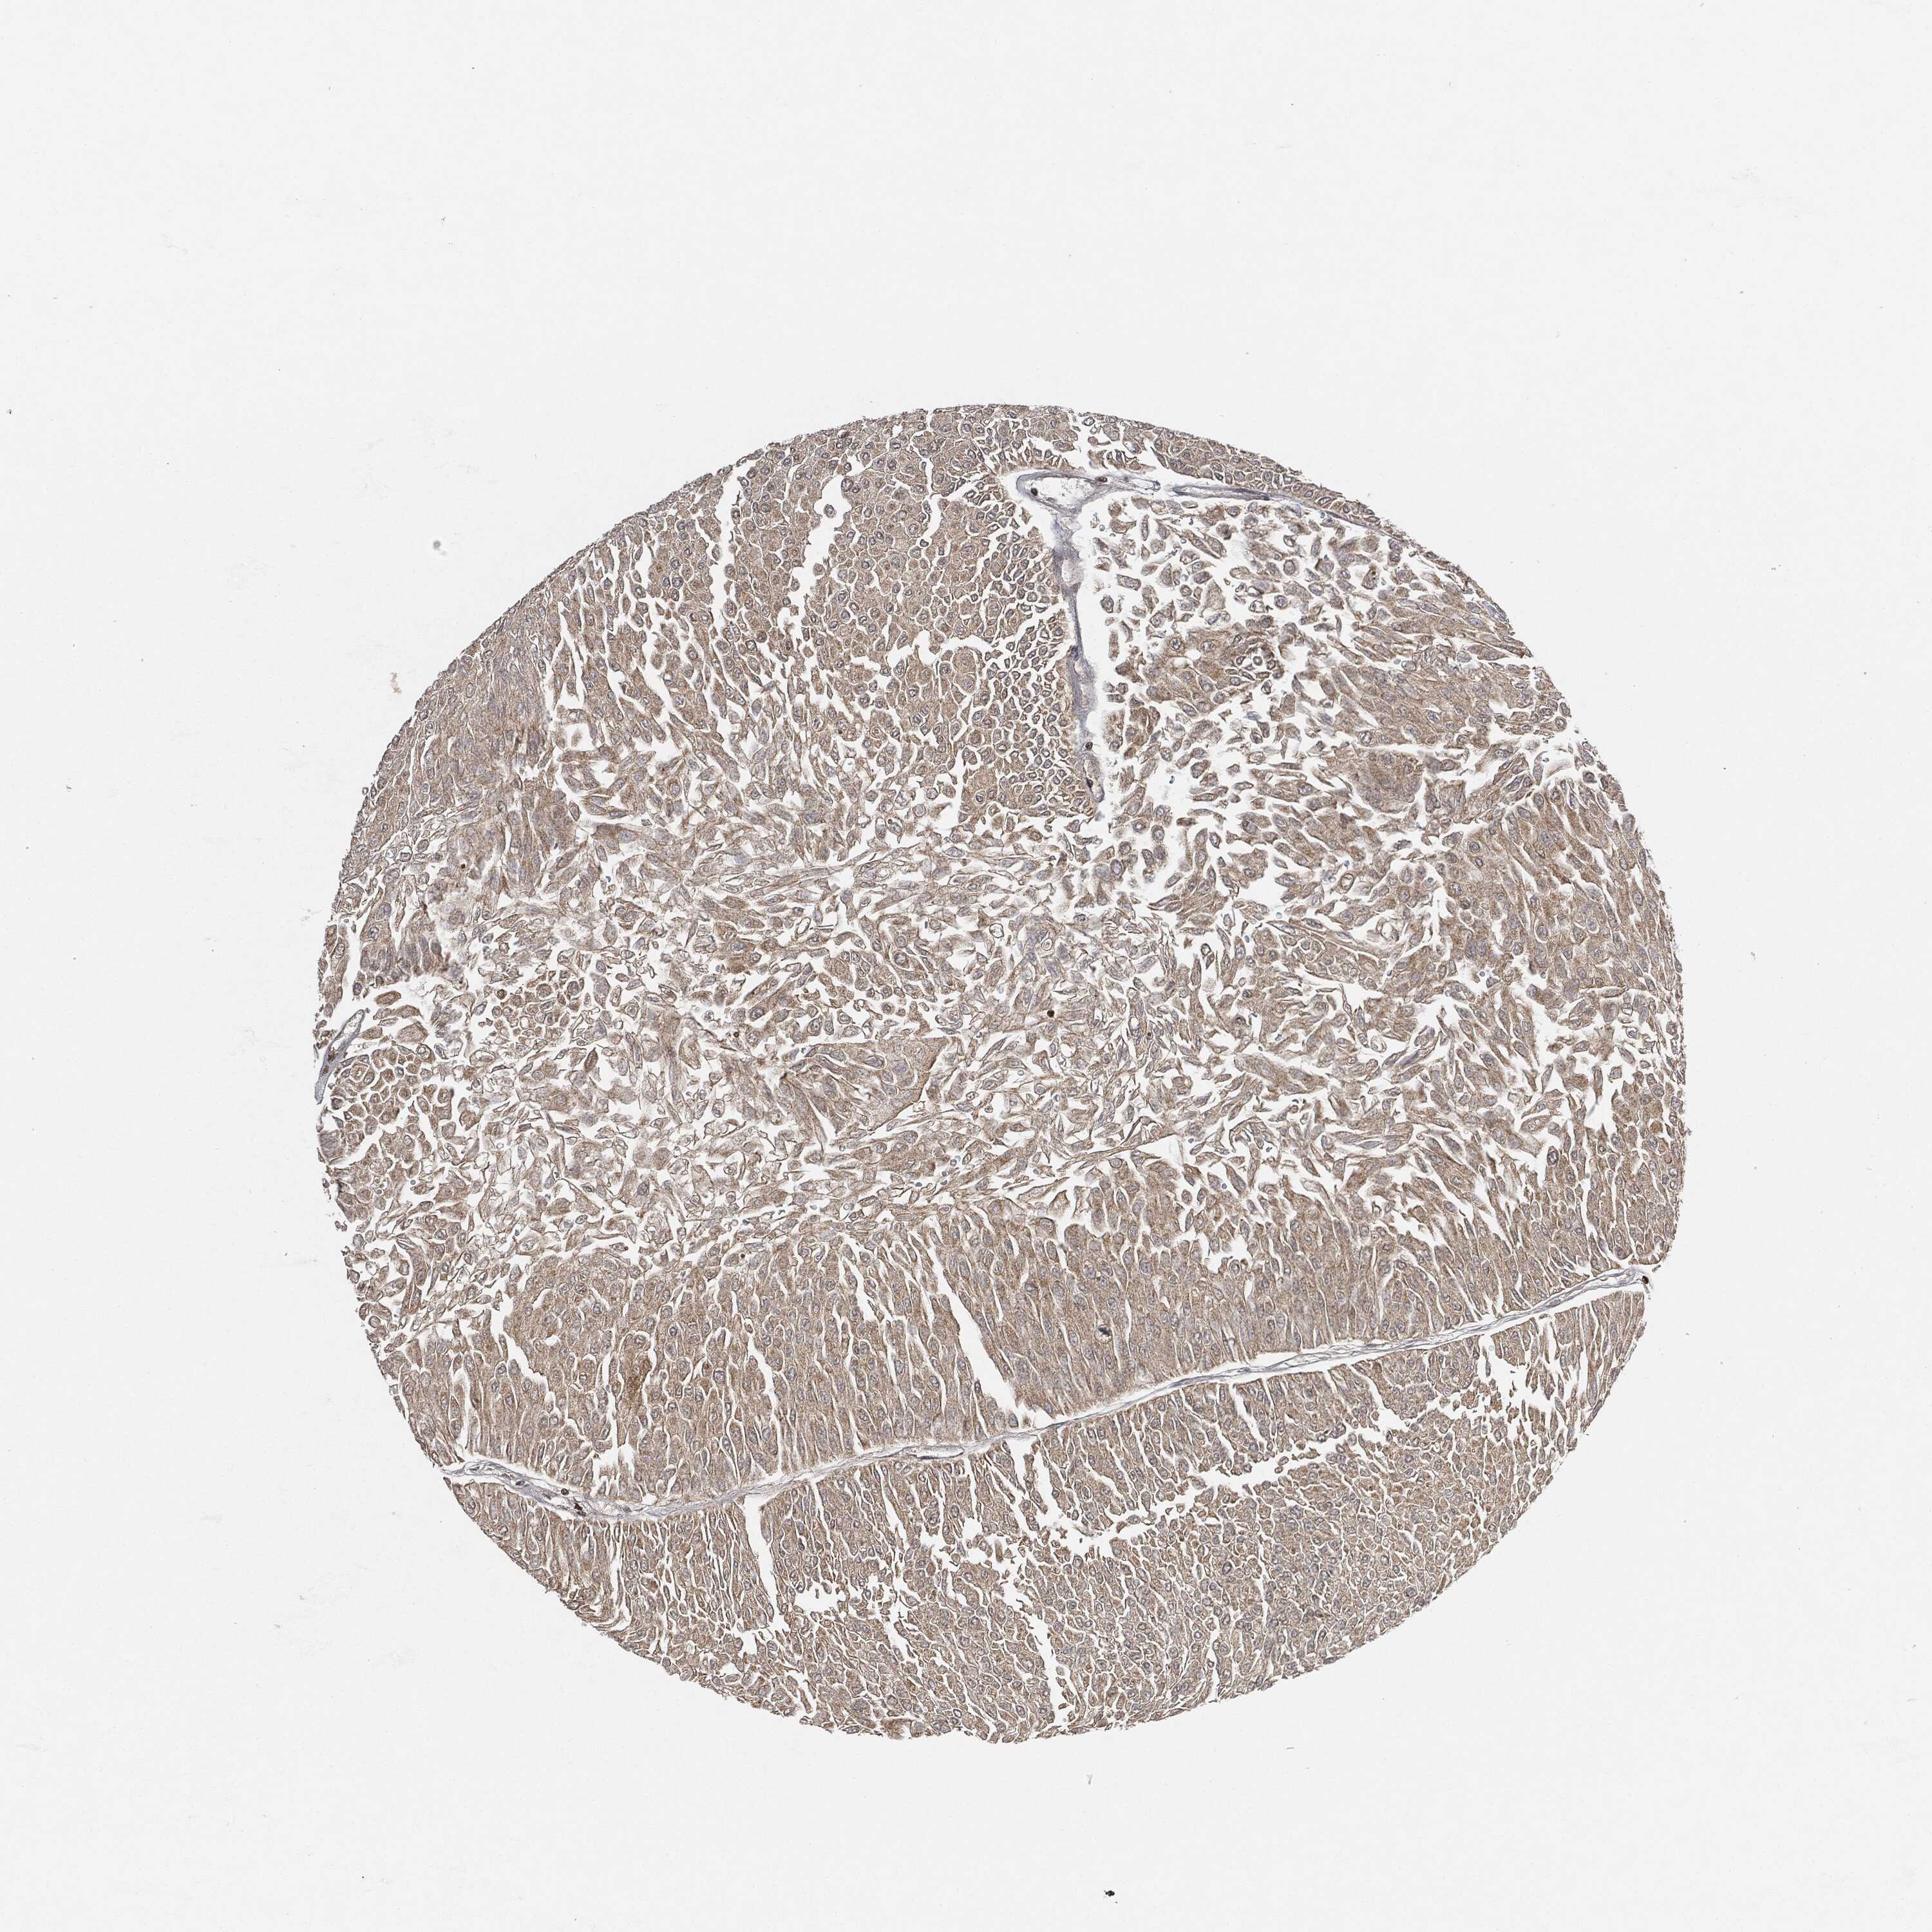

UROTHELIAL CANCER - Protein expressioni

A mouse-over function shows sample information and annotation data. Click on an image to view it in a full screen mode. Samples can be filtered based on level of antibody staining by selecting one or several of the following categories: high, medium, low and not detected. The assay and annotation is described here.

Note that samples used for immunohistochemistry by the Human Protein Atlas do not correspond to samples in the TCGA dataset.

Antibody stainingi

Antibody staining in the annotated cell types in the current human tissue is reported as not detected, low, medium, or high, based on conventional immunohistochemistry profiling in selected tissues. This score is based on the combination of the staining intensity and fraction of stained cells.

Each image is clickable and will lead to virtual microscopy that enables deeper exploration of all samples and also displays staining intensity scores, fraction scores and subcellular localization as well as patient and tissue information for each sample.

HPA001252

Urothelial carcinoma, High grade

Urothelial carcinoma, Low grade

Adenocarcinoma, NOS